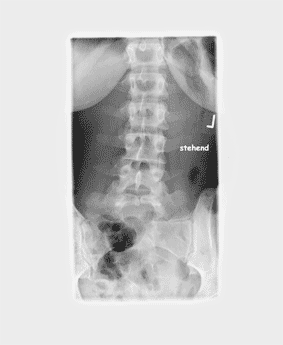

Daraufhin habe ich einen Termin beim Orthopäden vereinbart, der bei mir eine leichte Skoliose feststellte. Vermessen oder ähnliches wurde daraufhin nicht, weil das Ganze ja nicht so schlimm ist (Zitat von damals).

Hinzu kommt noch, dass ich (seit der Pubertät) auf der vorderen linken Seite meines Brustkorbes einen deutlich hervorstehenden Buckel habe und rechts die Rippen "reingehen".

Ein paar Röntgenbilder von damals (2004) füge ich dem Beitrag zu - ich hoffe, da kann man was erkennen